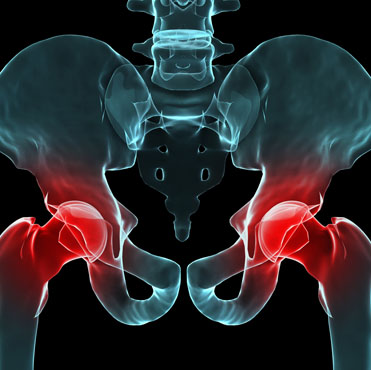

SICAPS, Es una empresa joven, la cual se creó después de trabajar en una compañía para el cuidado de la salud con la

confianza de estar estructurada y dirigida por especialistas en venta de productos quirúrgicos y técnicos especializados en

la salud, que se unificaron para ofrecer una satisfacción total; ya que se cuenta con los materiales, productos y

herramientas de la más alta calidad, con un servicio de primera. Nuestro personal está permanentemente actualizándose.

Hoy en día SICAPS ofrece productos, materiales quirúrgicos a personas particulares y empresas del giro hospitalario,

salud.